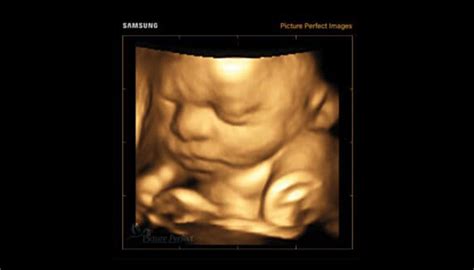

Ecografia în sarcină

Ecografia este o metodă imagistică esențială în monitorizarea sarcinii, utilizând unde sonore pentru a crea imagini în timp real ale fătului. Fiecare femeie va fi supusă unei ecografii la prima programare.

Ecografia de confirmare a sarcinii

O ecografie de confirmare a sarcinii este o investigație care utilizează unde sonore pentru a crea imagini în timp real ale fătului, fiind indicată după un test de sarcină pozitiv. Examinarea permite și excluderea unei sarcini ectopice, o afecțiune gravă, în care embrionul se implantează în afara uterului, cel mai frecvent în trompele uterine. La ecografie poți afla mai multe despre starea ta și câți copii vei avea, dar poți vedea și cum îi bate inima copilului. La ecografie îți vom spune tot ce vedem, cu excepția cazului în care există anumite lucruri pe care nu vrei să le cunoști, precum sexul copilului sau malformații care denotă probleme cromozomiale.

Există două tipuri principale de ecografii utilizate pentru confirmarea sarcinii:

- Ecografia transabdominală: realizată prin aplicarea unui transductor pe abdomenul inferior, cu ajutorul unui gel special. Acest tip de ecografie este de obicei preferat după a opta săptămână de sarcină.

- Ecografia transvaginală: indicată mai ales pentru diagnosticarea precoce a sarcinii, confirmarea viabilității prin detectarea bătăilor cordului fetal încă de la circa 6 săptămâni, și excluderea sarcinii ectopice. Această metodă nu necesită o vezică plină și permite o rezoluție superioară a imaginilor structurilor embrionare.

Ecografia pentru confirmarea sarcinii este realizată, în mod obișnuit, în primul trimestru, începând de la aproximativ 5 săptămâni de la prima zi a ultimei menstruații. Între săptămânile 6 și 7, activitatea cardiacă fetală este de obicei clar vizibilă. Confirmarea sarcinii și stabilirea vârstei gestaționale prin ecografie sunt pași esențiali pentru planificarea monitorizării prenatale și pentru identificarea eventualelor complicații timpurii.

Morfologia fetală

Morfologia fetală este o evaluare ecografică detaliată a fătului, care se efectuează în fiecare trimestru de sarcină și permite medicului imagist să studieze sistematic evoluția organelor fetale, pentru a detecta eventuale defecte, precum malformații ale capului, ale feței, lipsa unor membre, anomalii renale sau cardiace.

- Prima morfologie (Trimestrul I): se efectuează începând cu săptămânile 11 sau 12 de sarcină. În asociere cu testarea serologică (dublu test), este cea mai fidelă modalitate de depistare a anomaliilor cromozomiale. Se urmăresc opt semne ultrasonografice de diagnosticare a eventualelor anomalii cromozomiale.

- Morfologia fetală de Trimestrul II: urmărește aspecte precum dezvoltarea organelor fetale, stabilește sexul bebelușului (la cererea părinților), analizează mărimea și localizarea placentei, apreciază lichidul amniotic și colul uterin, precum și fluxurile sanguine. Permite evaluarea cu maximă precizie a dezvoltării bebelușului și organelor acestuia.

- Morfologia fetală de Trimestrul III (Ecografia Morfologică Placentară): este foarte importantă pentru stabilirea gradului de maturare a placentei, a cantității de lichid amniotic și eventual, pentru depistarea precoce a insuficienței de creștere intrauterină a fătului. Se efectuează o examinare Doppler minuțioasă și o ecocardiografie fetală.

Ecografia de morfologie fetală reprezintă o investigație imagistică esențială în cadrul monitorizării sarcinii, având un rol central în evaluarea dezvoltării fetale și a stării generale de sănătate a fătului. Principalul scop al ecografiei de morfologie fetală este examinarea detaliată a structurilor anatomice ale fătului pentru a detecta eventualele anomalii congenitale sau malformații. Ecografia permite determinarea cantității de lichid amniotic (indicele lichidului amniotic - AFI), ceea ce poate indica probleme precum oligohidramniosul (lichid insuficient) sau polihidramniosul (exces de lichid).

Ecografia morfologică nu te expune la iradiere și este o procedură complet nedureroasă. Știm că sarcina este cea mai frumoasă, dar și cea mai provocatoare perioadă din viața ta!